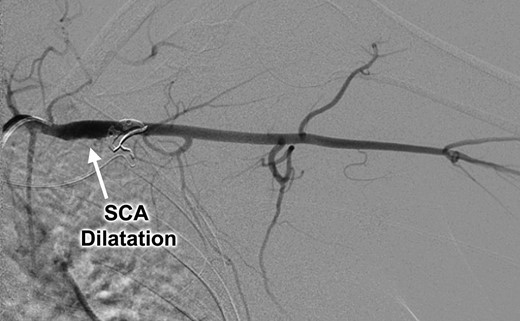

Catheter-based left subclavian arteriogram demonstrating post-stenotic aneurysmal dilatation of the subclavian artery (SCA).

Clinical evaluation revealed an absence of palpable pulses at the left wrist but adequate arterial circulation to the hand at rest, with brisk capillary refill in the fingers and no signs of digital embolism. Upper extremity strength, sensation and range of motion were normal and there were no signs of swelling, edema or cyanosis to suggest venous obstruction. The patient was brought to the operating room for thoracic outlet decompression using a left supraclavicular approach. After mobilizing and rotating the scalene fat pad on a lateral pedicle, the phrenic nerve was identified in its expected position on the surface of the anterior scalene muscle; however, the subclavian artery was not found within the scalene triangle adjacent to the brachial plexus, but in front of the anterior scalene muscle insertion on the first rib, in the costoclavicular space directly posterior to the phrenic nerve (Figs 4 and 5). Thoracic outlet decompression was performed with anterior and middle scalenectomy, brachial plexus neurolysis and first rib resection [10]. Direct inspection and intraoperative left upper extremity arteriography demonstrated post-stenotic dilatation of the subclavian artery and chronic occlusion of the brachial artery with abundant collaterals. The affected segment of the subclavian artery was resected and found to contain an ulcerated lesion with thrombus (Fig. 6), and the artery was reconstructed with a 6-mm diameter cryopreserved femoral artery interposition graft (Fig. 7). The patient was discharged on postoperative Day 3 taking a direct oral anticoagulant and she was clinically stable during subsequent follow-up.